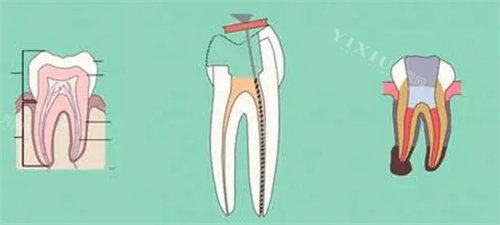

作为连锁的口腔医疗巨头,拜尔口腔在上海、北京等一线城市深耕20年后,2023年正式入驻沈阳于洪区。其核心优势在于设备投入堪称“行业头牌”:斥资千万引进的法国锐柯KODAK9500锥形束口腔CT,可实现76μm级真实影像分辨率,种植牙术前骨量评估误差率低于0.3%;美国YSGG水激光设备能精细切割软组织,儿童拔牙出血量减少80%;德国Zeiss手术显微镜将根管治疗成功几率提升至99.2%。

这家位于泰华林家园底商的诊所,凭借“医生即老板”的运营模式,在周边居民中积累起极高信任度。建立人张爱群医师从业25年,擅长复杂根管治疗和活动义齿修复,其创新的“四手操作流程”将单颗牙治疗时间缩短40%。